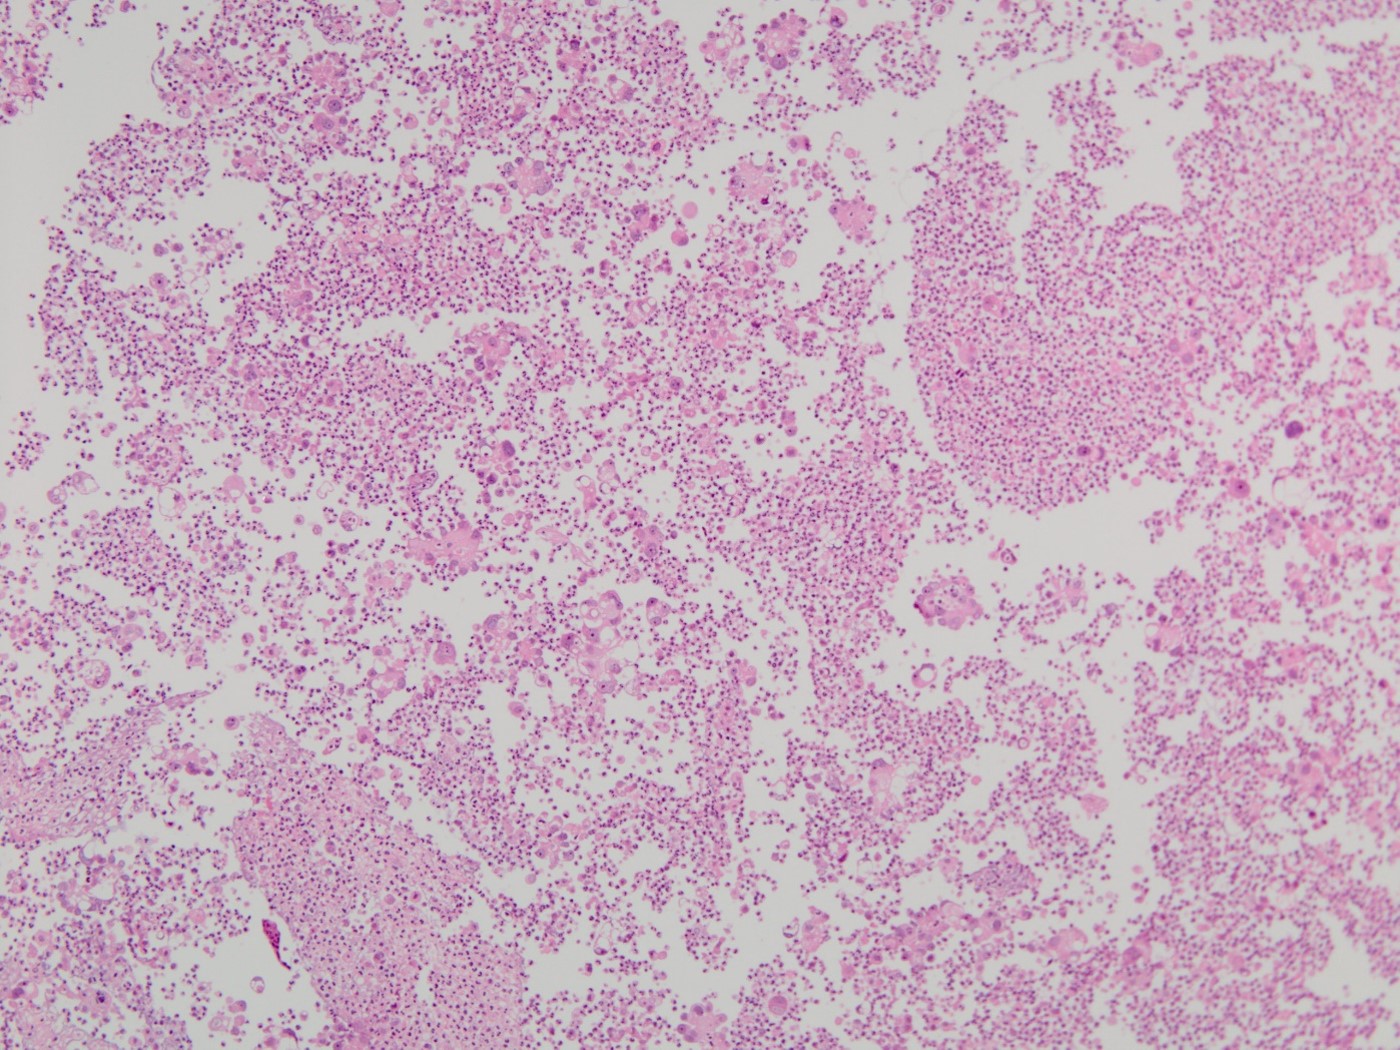

炎症性細胞を背景に、核形の不整や核クロマチンの増量、明瞭な核小体を認める異型細胞が孤立散在性もしくは集塊状で出現していた。核は偏在し、PAS染色で陽性となる胞体(粘液)もみられ、腺癌細胞であると考えた。女性であることから肺・卵巣・乳腺・胃・結腸などの可能性が推測された。

組織所見

心嚢水のセルブロックと肺生検において、免疫組織化学染色(TTF-1抗体)で、腺癌細胞に陽性所見が認められた。肺腺癌の心嚢への転移浸潤と診断した。